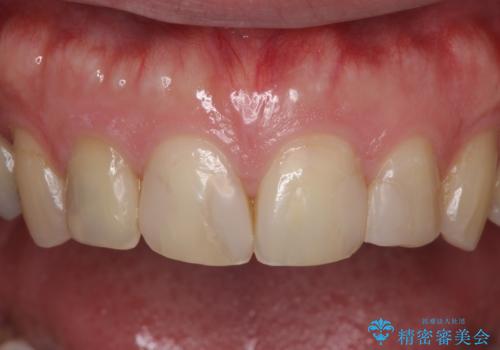

- 前歯の見た目を主訴にご来院された患者様です。虫歯治療を複数回繰り返して、前歯のつめものがつぎはぎになっていました。

当初は1番目立つ1本だけをご希望でしたが、相談の結果、隣の歯(神経が抜いてあり金属が入っている歯)と2本同時に製作することになりました。

患者様は前歯の見た目の改善を主訴にご来院されました。上の前歯6本とも古いつめものがつぎはぎになっていましたが、まずは1番目立つところを治すことをご希望でした。相談の結果、今回は2本できれいになるように工夫しました。